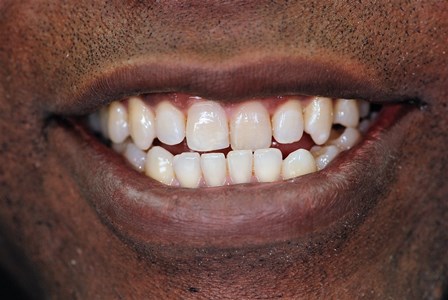

Before

After